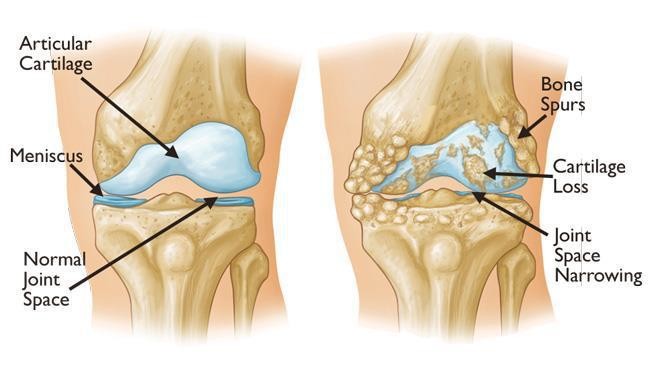

각각의 뼈의 면에는 관절의 마찰을 줄이기 위해 부드러운 연골이 둘러싸여 있다. 2-3mm 두께로 구성되어 있으며, 이러한 연골이 없다면 관절은 충격에 취약해지고, 운동도 매끄럽지 못하게 된다.

| ▲ 각각의 뼈의 면에는 관절의 마찰을 줄이기 위해 부드러운 연골이 둘러싸여 있다. 2-3mm 두께로 구성되어 있으며, 이러한 연골이 없다면 관절은 충격에 취약해지고, 운동도 매끄럽지 못하게 된다. |

한편 파열된 연골판이 제대로 관리되지 않아 뼈의 연골을 건드려 닳게 만드는 상황에 이르면, 무릎의 통증과 운동제한은 더욱 심각해진다. 심지어 무릎을 수동으로 굴곡, 이완 시키면 뼈가 갈리는 사각사각 소리도 들을 수 있다.